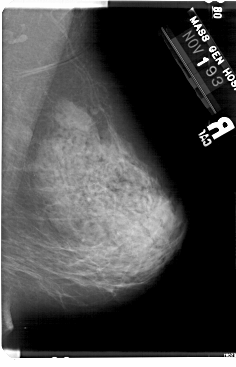

A_1732_1.LEFT_CC

LEFT_CC LINES 5491 PIXELS_PER_LINE 3511 BITS_PER_PIXEL 12 RESOLUTION 43.5 OVERLAY